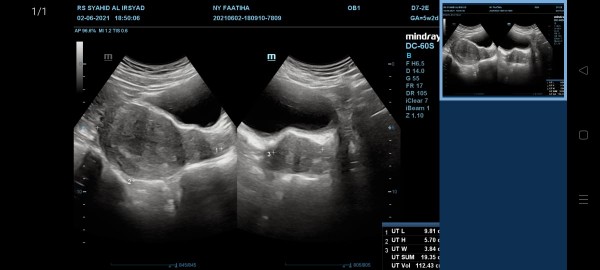

5 weeks

Bun ini aku usg pertama kli usia 5 minggu ini udh ada dedenya kan ya ? ?